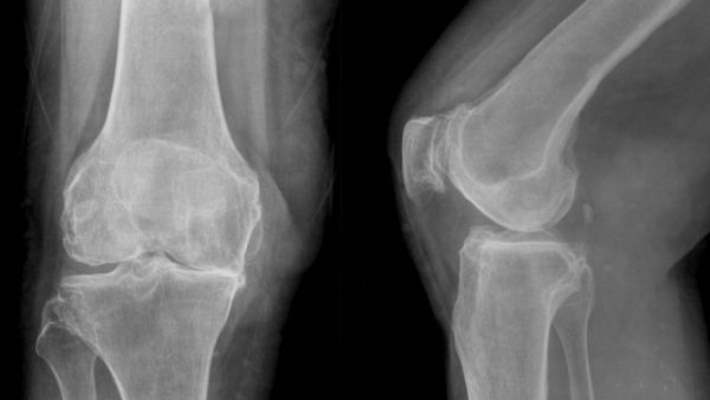

Bacak kemiğindeki kırığın türü ve yeri, hangi tedavinin gerekli olduğunu belirleyecektir.

- Bir acil servis doktoru geçici plaster alçıyla pek çok kırık türünü tedavi edebilir, sonrasında sizi takip için ortopedi doktoruna yönlendirecektir. Fakat uyluk kemiği veya incik kemiği kırıklarıyla acilen ortopedi cerrahının ilgilenmesi gerekir. Bu da alçı, hatta ameliyat anlamına gelebilir.

- Kemikler, iyileşmesi için birkaç yöntemle sabitlenebilir.

- Genellikle bir plaster veya alçı kullanılır.

- Eğer ameliyat gerekiyorsa kırık kemik uçlarını sabit tutmak için iğne, vida ve metal plakalar veya tel kullanılabilir.

- Uyluk veya incik kemiğinin orta kısmındaki bir kırık için kemiğin ortasından metal bir çubuk yerleştirilir. Bu da ancak bir ameliyathanede yapılır.

- Uyluk veya bacak kemiği kırığının iyileşmesi genellikle ağırlık yüklemeksizin 6-12 hafta sürer.